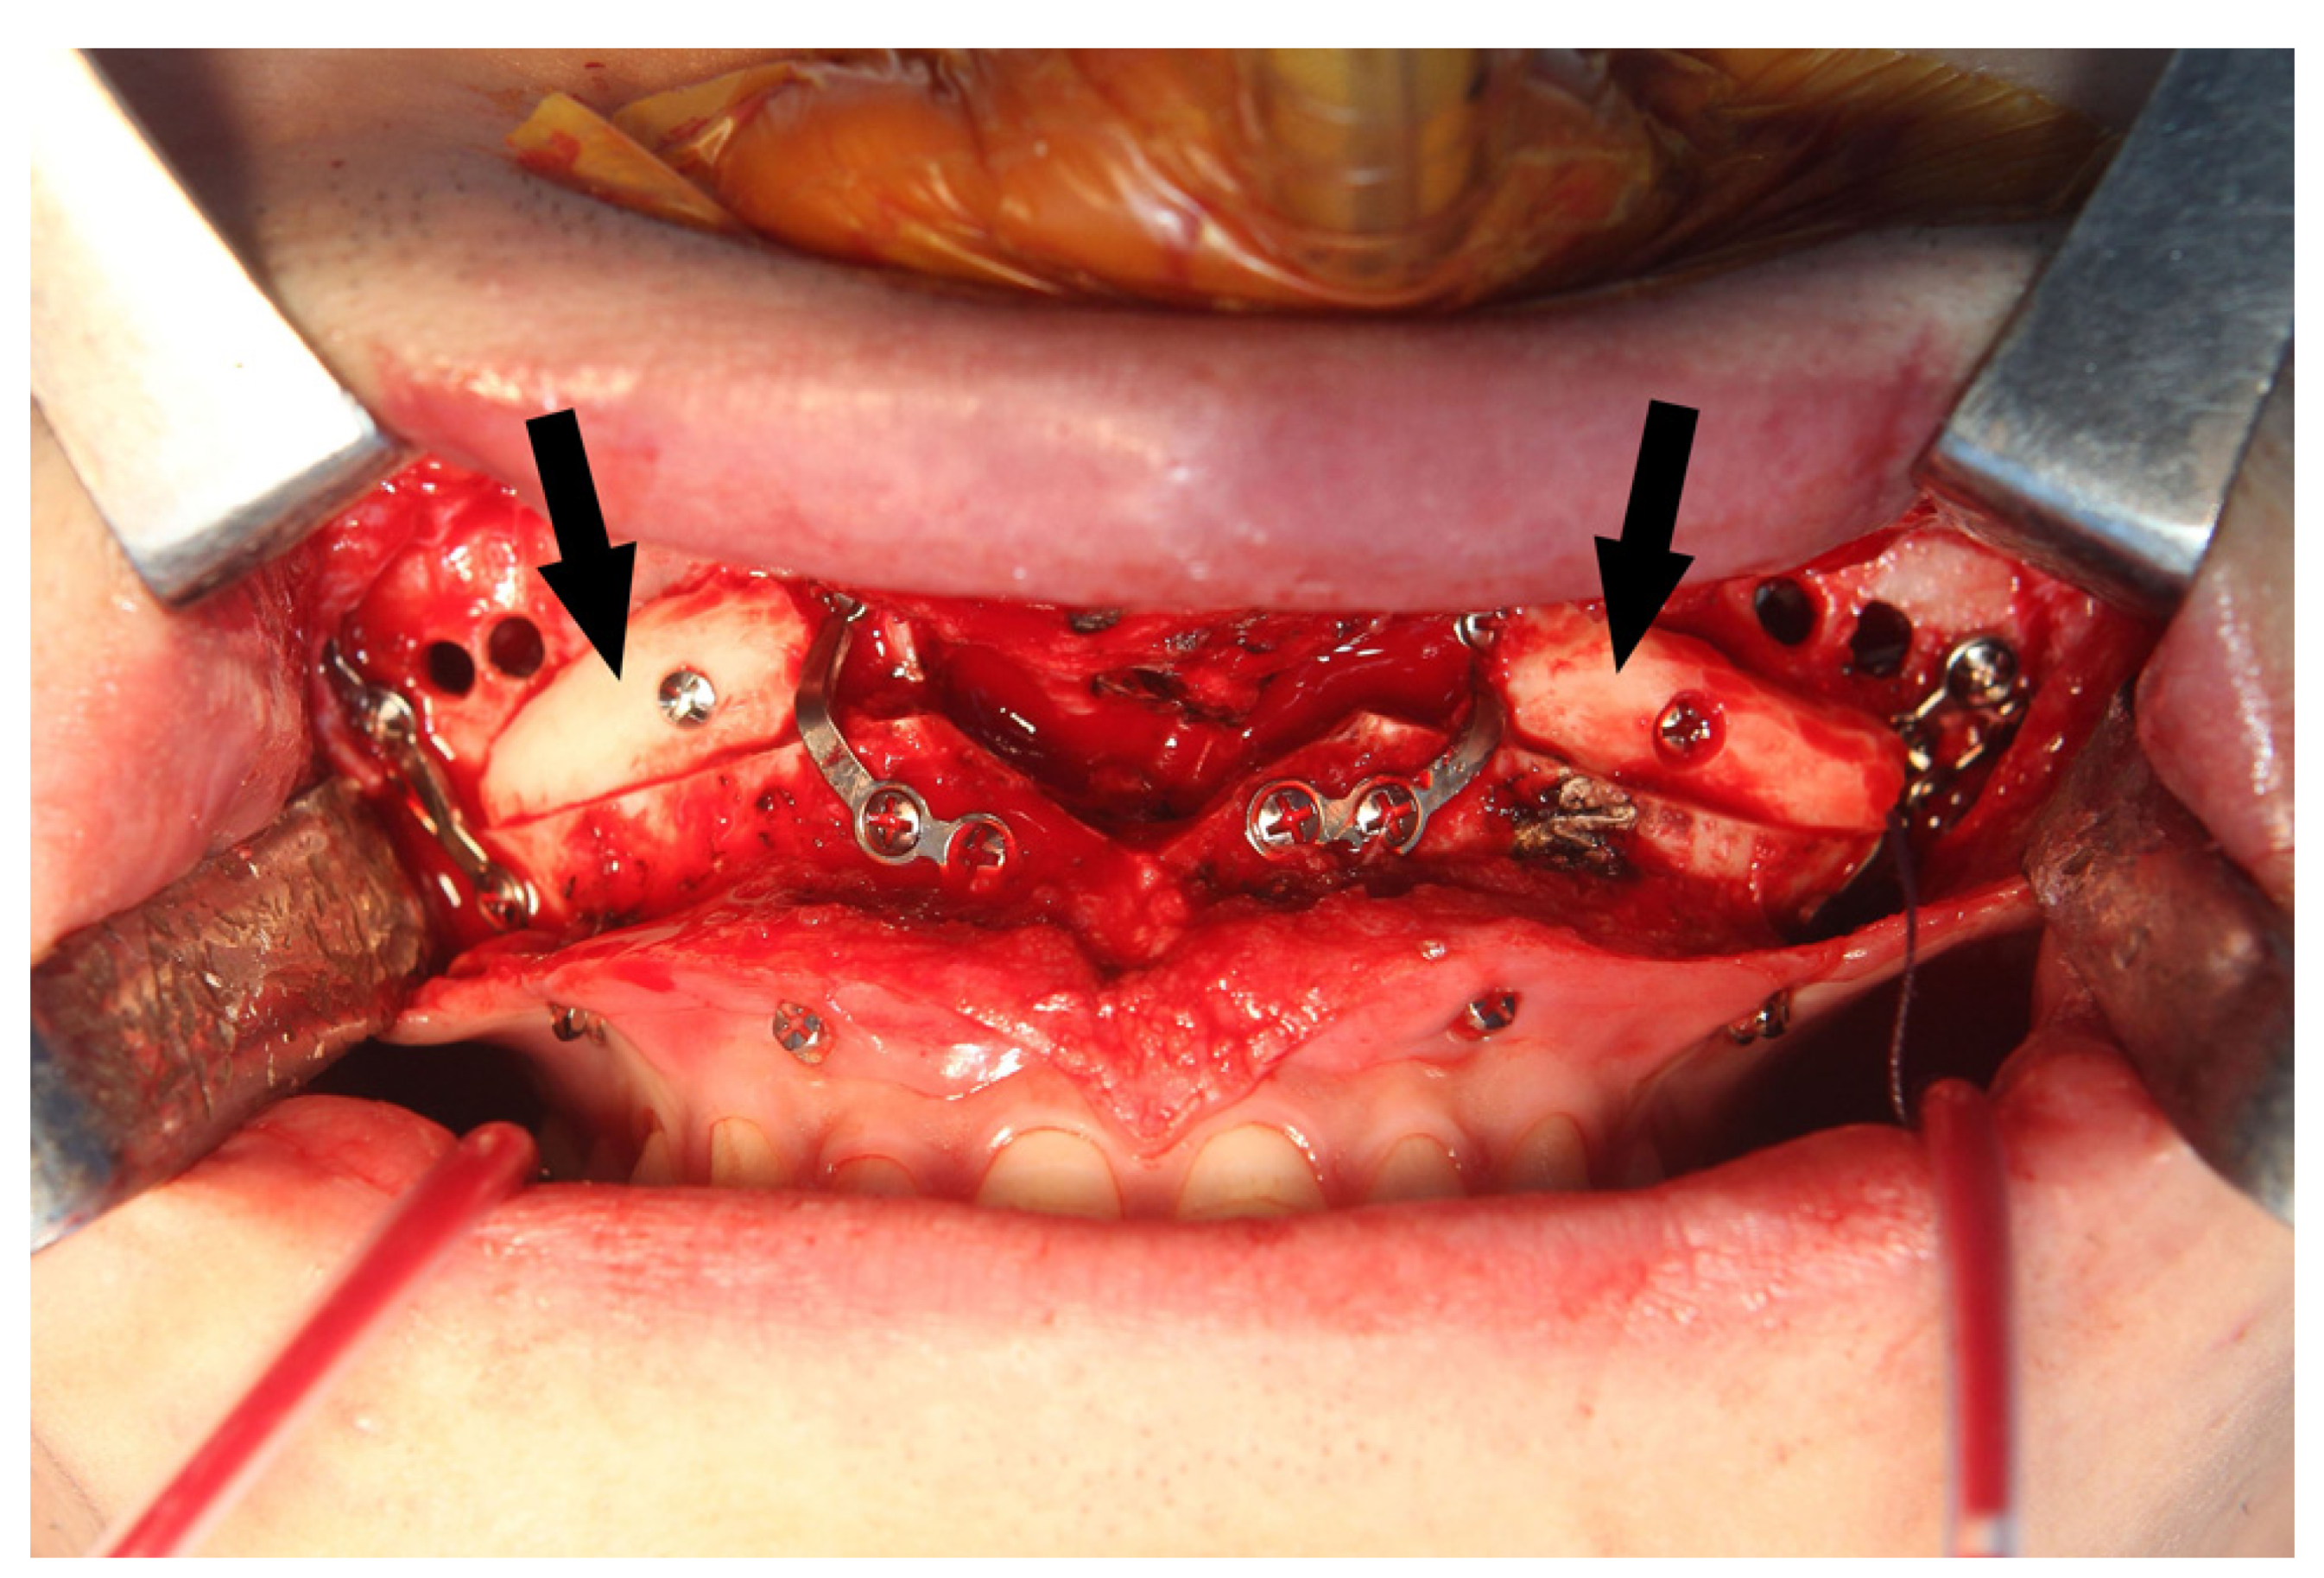

During the Le Fort I osteotomy, autogenous block bones were grafted at the bony gap of the anterior maxilla for postoperative stability of the maxilla and for achieving a more efficient drainage of the maxillary sinus by minimizing the communicating spaces (Figure 6).

Figure 6.

Autogenous block bone (arrows) was grafted at the bony gap of maxillary sinus wall for a more efficient drainage of maxillary sinus.